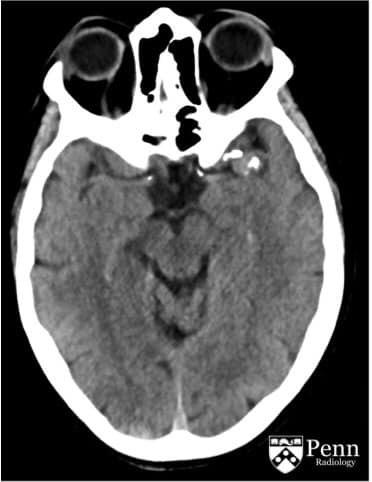

Paciente femenina de mediana edad que acude al servicio de urgencias por presentar convulsiones por primera vez, tras realización de CT de craneo se obtienen las siguientes imagenes:

La lesion evidenciable se encuentra:

a) extraxial

b) intraxial

Probable estirpe etiologica de la lesion:

a) glial

b) dural

c) vascular

d) ependimaria

Las areas hiperdensas sugieren?:

a) sangrado activo

b) sangrado antiguo

c) calcificaciones vasculares

d) fragmentos oseos